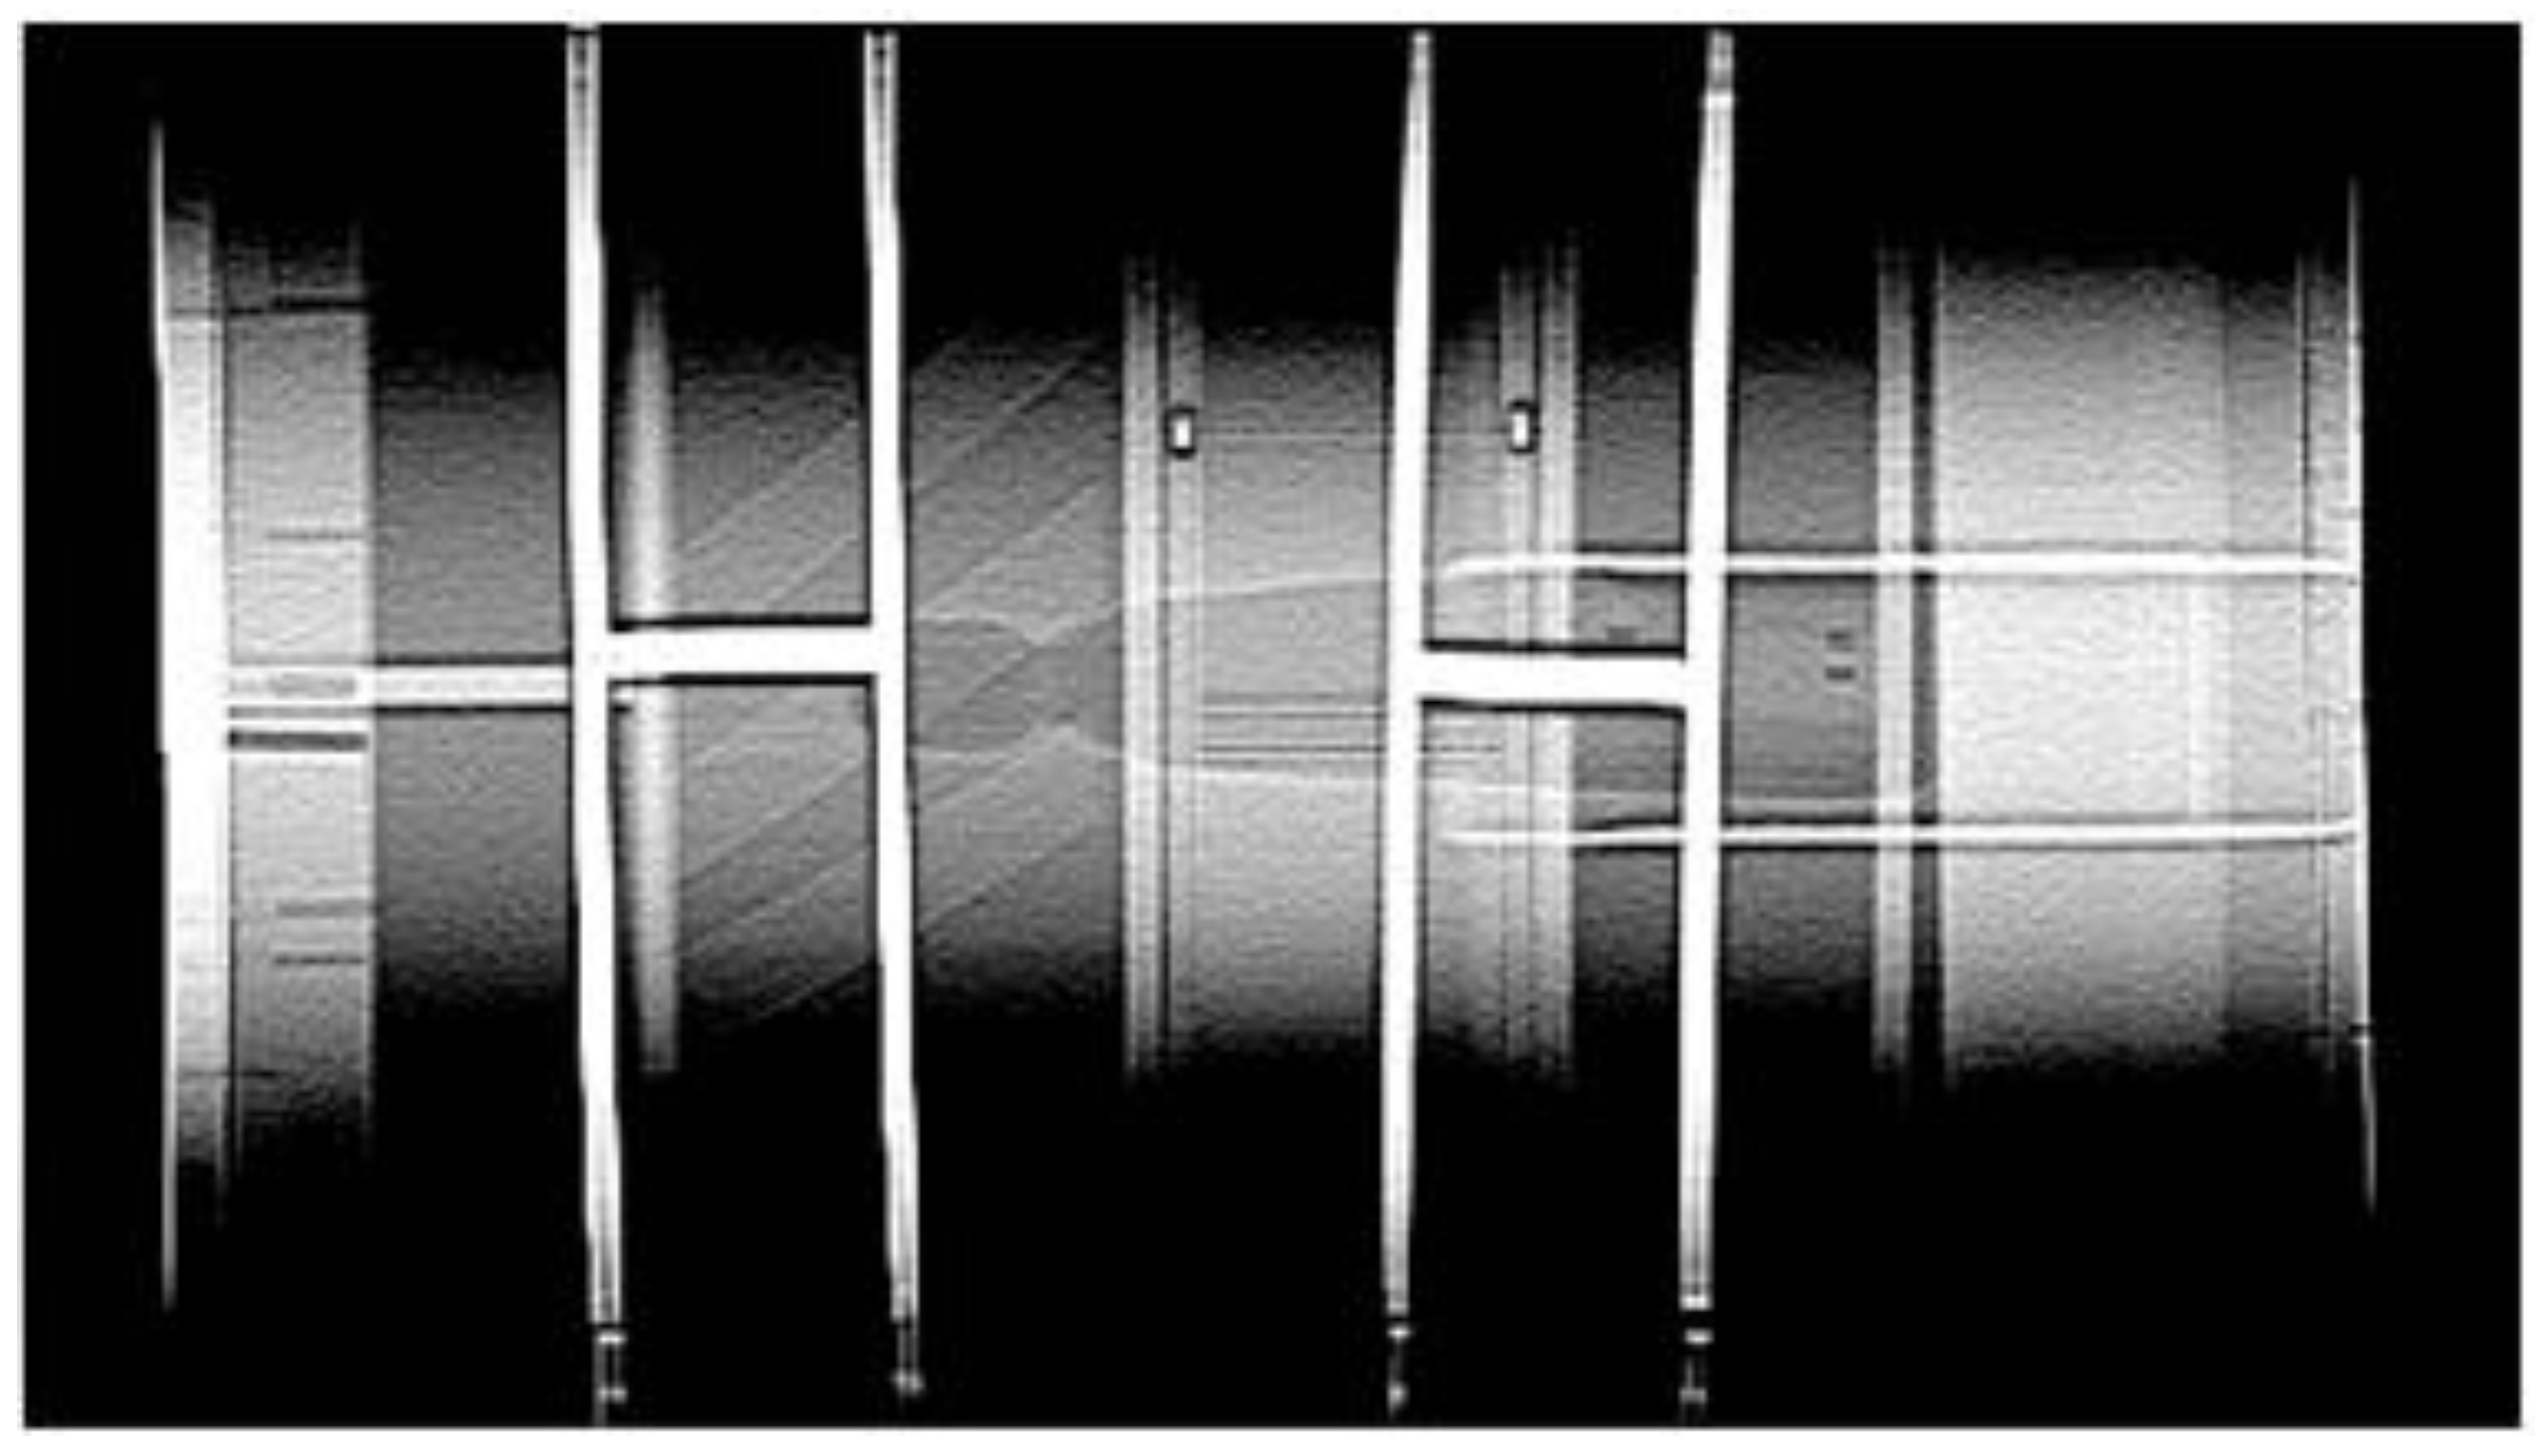

The imaging conditions were standardized to 120 kVp, 250 mAs, with a beam width of 10 mm. The exposure field was set to over 25 cm, with a pre-exposure field of 25 cm. Standard reconstruction algorithms were applied accordingly, as illustrated in Figure 2 [13].

Figure 2.

(a) Spatial resolution area; (b) contrast resolution area.